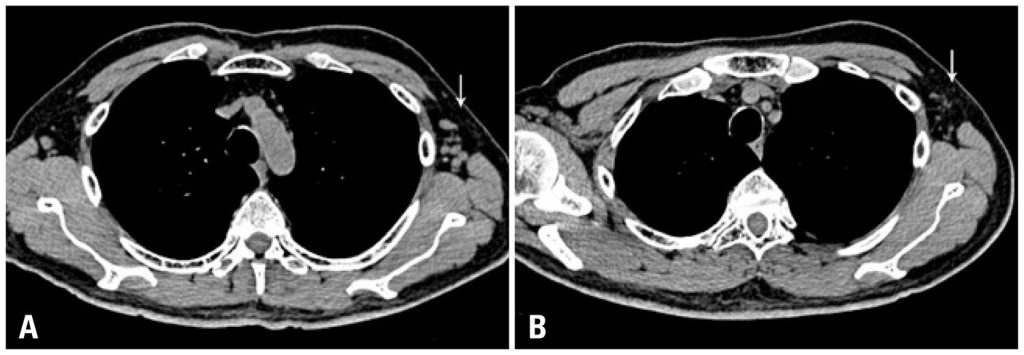

Os autores relatam o caso de um paciente de 70 anos com leucemia linfóide crônica que apresentou subsequentemente um carcinoma papilífero da tireóide com metástases para linfonodos regionais. O paciente foi tratado com tireoidectomia total cirúrgica com exérese de linfonodos regionais e cervicais e radioiodoterapia (I-131). A pesquisa de corpo inteiro protocolar de controle 4 dias após a dose radioativa mostrou captação de I-131 em ambas as axilas e mesmo nas regiões inguinais. PET/CT mostrou discreta captação de FDG-F-18 em um linfonodo da axila esquerda. A biópsia por agulha fina guiada por ultrassom deste linfonodo identificado por SPECT/CT com I-131 e PET/CT com FDG-F-18 revelou células linfomatosas e foi negativa para tecido tireoidiano e conteúdo de tireoglobulina. Os hemogramas sequenciais feitos rotineiramente após tratamento com radiações mostraram uma acentuada queda até retorno aos valores normais de leucócitos e de linfócitos (absolutos e relativos), que continuavam normais no último controle 19 meses após a administração do radioiodo. Tomografia computadorizada de tórax mostrou uma redução em tamanho de linfonodos axilares e para-aorticos. Por imunohistoquímica, as células da linhagem linfoide B decresceram de 52% antes da radioiodoterapia para 5% depois do procedimento. Os autores conjeturam sobre uma possível expressão de symporter de iodeto de sódio pelas células deste linfoma, à semelhança de outros tumores não tireoidianos, tais como células de câncer da mama.